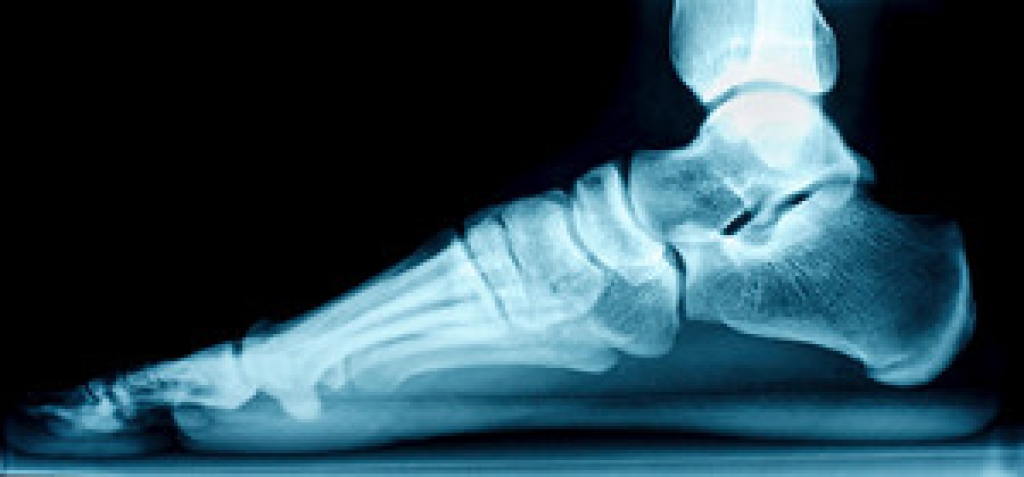

Cracked Heels

Cracked heels appear unappealing and can make it harder for you walk around in sandals. Aside from looking unpleasant, cracked heels can also tear stockings, socks, and wear out your shoes. There are several methods to help restore a cracked heel and prevent further damage.